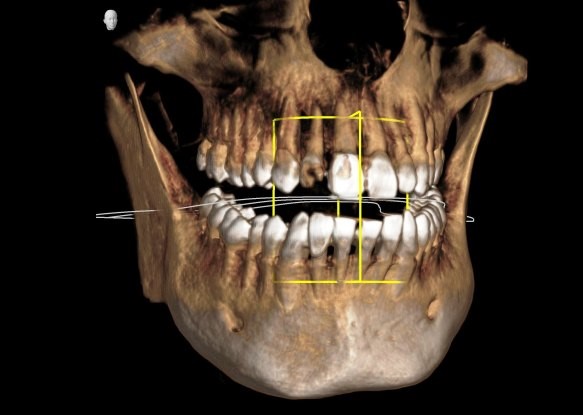

CT撮影をすることで

3次元の情報を得ることができます。

CTとは、コンピューター断層撮影

(Computed Tomography)の略称で、

放射線を照射することで、

3次元的(3D)に描画することが可能です。

5. 理解しやすい説明ができる

3D画像を使って説明することで、

治療が必要な理由や手術の方法を

わかりやすく伝えることができます。